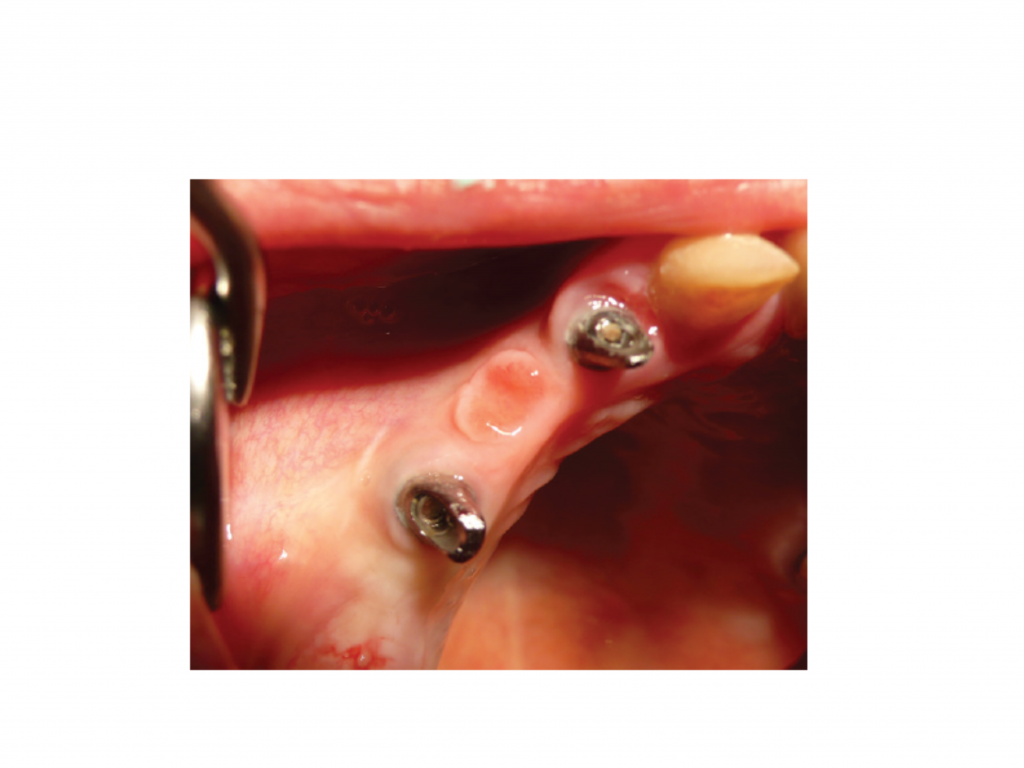

Fig. 9 Prosthetic treatment: clinical situation with installed PEEK abutment 4 months after implant placement